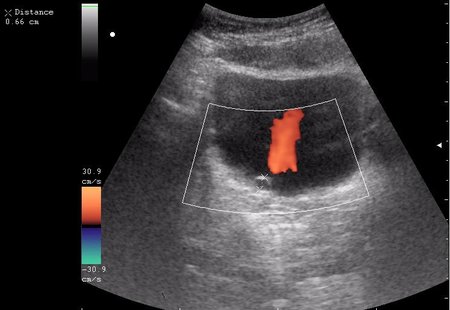

Богу богово, кесарю - кесарево (я про анализы и клинические данные). На сонограммах неубедительно продемонстрирован осадок да и стенки м.п. не утолщены.

зато какое наполнение! а осадок убедительный! а же не 7-кой смотрела!На сонограммах неубедительно продемонстрирован осадок да и стенки м.п. не утолщены.

Сравните

Продольное сканирование мочевого пузыря После легкой перкуссии мочевого пузыря